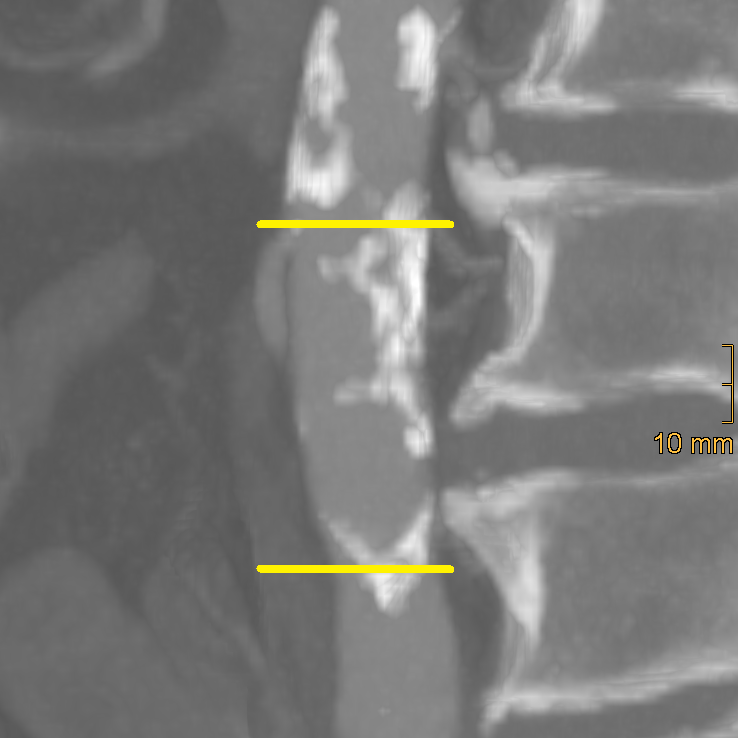

2.2. Assessment of Vascular Calcification

2.2.1. Abdominal Aortic Calcification

2.2.2. Iliac Artery Calcification